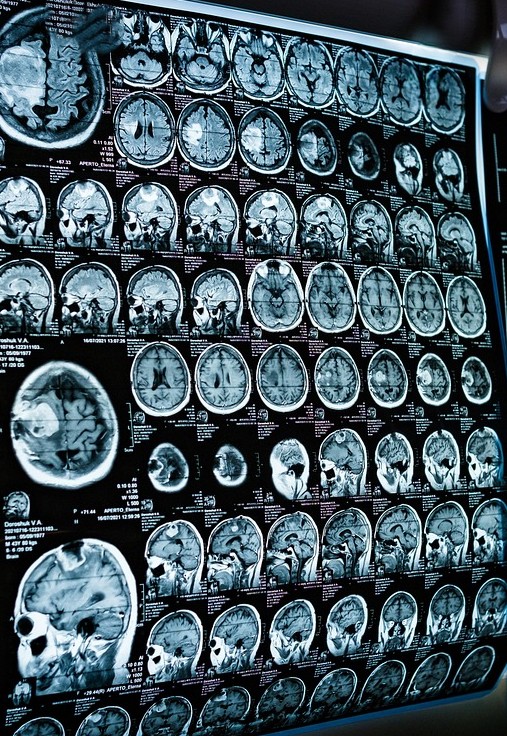

頭痛が起こったりすると「脳の病気では?」と不安になりますよね。 その気持ち、よくわかります。 症状が軽いからといって軽視していいものではないのです。 脳の疾患を的確に診断し、悪化予防の治療を受けてもらいたい。 脳の疾患がない人には安心してもらいたい。それが外来のやりがいだと思っています。 身体に異変を感じるようなことがあれば、早めにお越しください。 早期検査と早期発見で、病気の悪化防ぐこともできるのです。